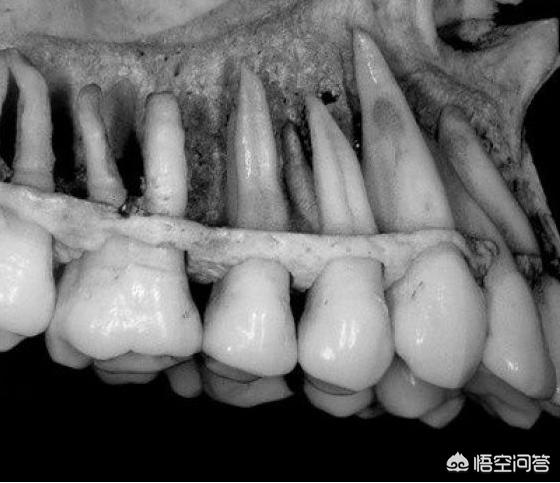

我们先来看看牙齿的形状。看看它们在口腔里面的静态构成。

大家注意到了没有?牙齿可不是很浅的”种植“在牙床肉上面,而是很深很深的长在肉里面牙床里面的,有的竟然是外露部分的三倍有余。为了增加牙齿的牢固度,中间部分的牙齿根部都是叉子形状的,板牙部分为了增加耐磨的力度和面积,他们的根部是粗粗的柱子桩的样子。所以这么结实牢固的牙齿,它的根部发展和延伸,必然会影响到人面部的脸。